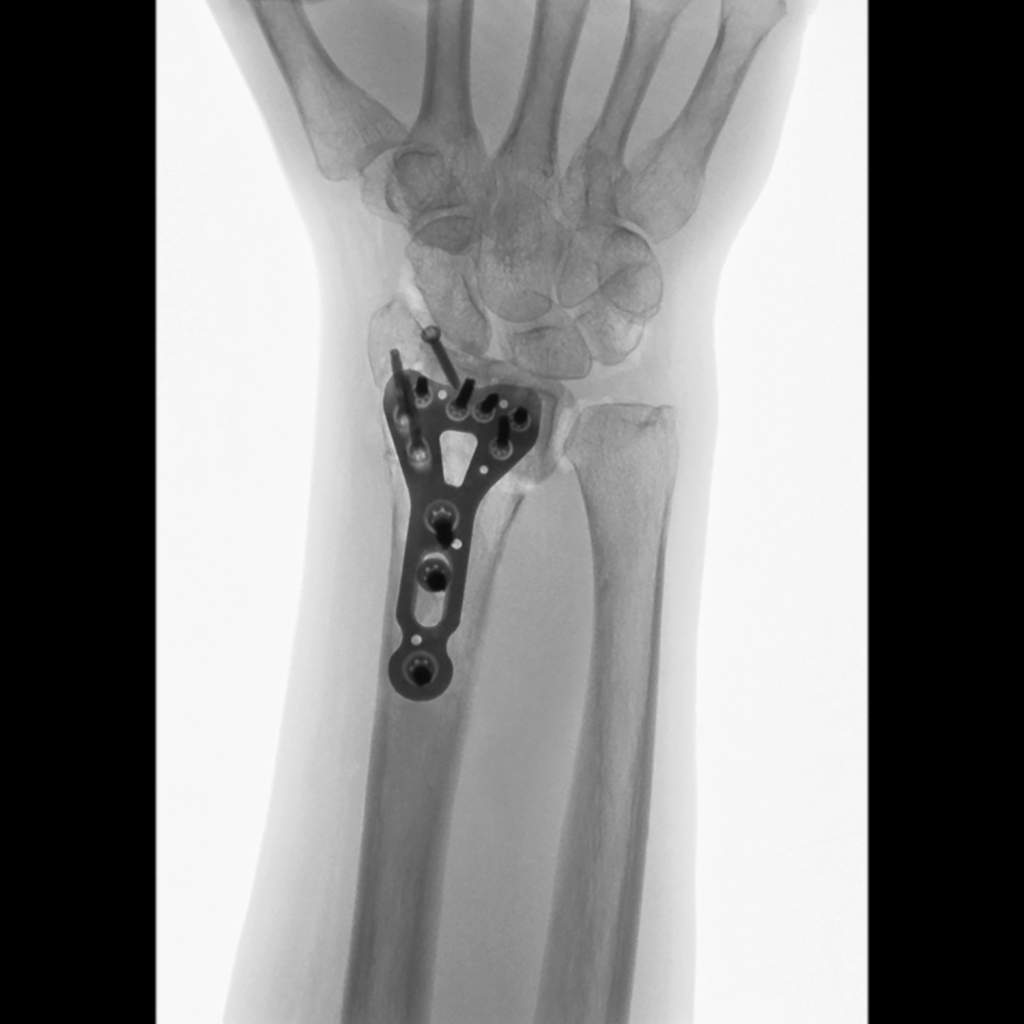

The hand surgery team operates on 12 to 16 cases per week in three of eight operating rooms. Additionally, patients come in for consultations. On average, two to four people with climbing injuries seek advice each week. “For example, they want a realistic assessment of when they will be able to climb again if their general practitioner says it is no longer possible,” explains the hand surgeon. “In fact, we operate on only a handful of them each year because most climbing injuries can be treated without surgery.” Prof. Schweizer and his team most frequently operate on people with carpal tunnel syndrome and fractures. They also often perform corrective osteotomies. These are necessary when fractures have not been treated or have been treated inadequately. If the forearm bones grow together incorrectly, it can lead to restricted movement and pain. During a corrective osteotomy, the surgeon sections the affected bone so that the pieces can be repositioned and secured with screws in proper alignment. “In complex cases, planning such an operation can take several hours,” emphasizes Prof. Schweizer. To ensure the bones are precisely fitted together at the correct angle, the hand surgeon uses computer assisted research and development (CARD) blocks customized for each patient. Based on a Japanese model, the physician developed these 3D-printed templates himself and introduced them at Balgrist. They facilitate precise sawing and screw placement. Operations using CARD blocks now take place weekly, setting the university hospital apart from other institutions. “Depending on the case, we are 30 to 50 percent faster. A shaft osteotomy takes only two hours instead of four,” explains Prof. Schweizer.

Working closely with his surgical team, Prof. Schweizer takes advantage of the technologies at his disposal: These include 3D blocks and mini C-arms, which provide reliable images for checking the position of bones, wires, screws, and plates. For Prof. Schweizer, his work and hobby go hand in hand because “When operating, it’s definitely an advantage to have a bit of strength.” His good finger strength enables him to sustain his body weight on even the smallest climbing handholds, as well as to safely and precisely guide surgical instruments during procedures.